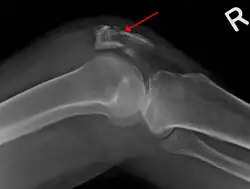

A fracture of the patella seen on a lateral view | |